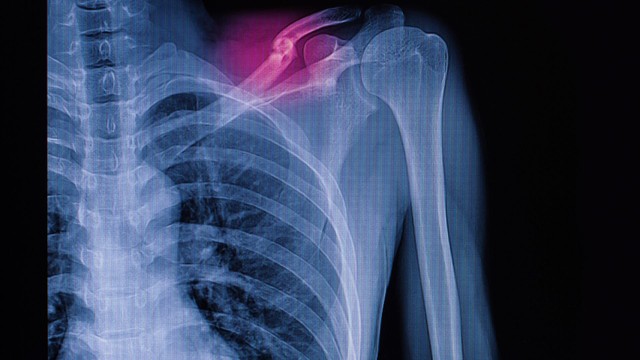

X-quang xương đòn là một kỹ thuật chẩn đoán hình ảnh phổ biến, giúp bác sĩ đánh giá tình trạng của xương đòn và các cấu trúc liên quan. Đây là phương pháp quan trọng để phát hiện gãy xương, tổn thương hoặc các bệnh lý khác ở vùng vai và ngực, mang lại thông tin chính xác để đưa ra phương án điều trị phù hợp.